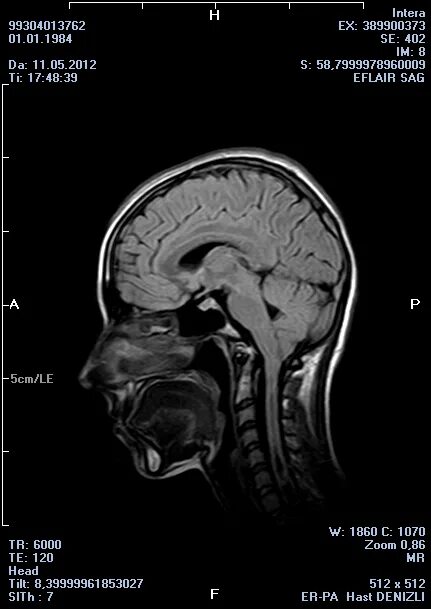

Код мкб арнольда киари